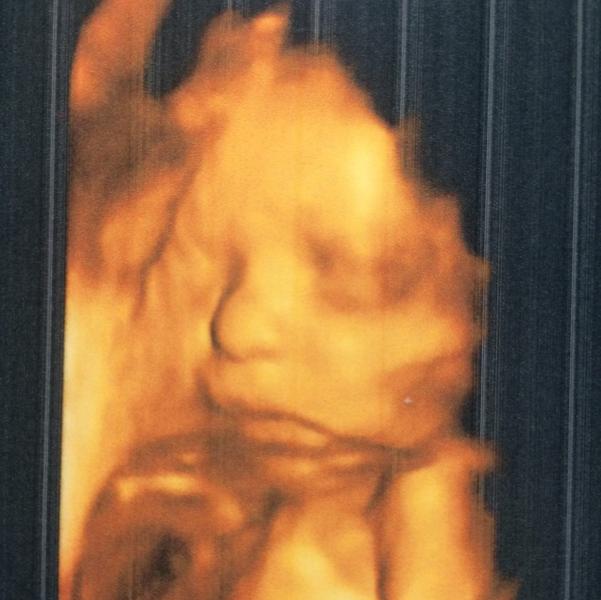

Нашла я все же фото своего птенчика 😻 Делала Написат на 28-29 неделях. Завтра на узи к Айшат , жду что расскажут мне о моем львёнке на 34 неделе его прибывания в моем пузике. Как же летит время , вроде недавно увидела 2 полосочки, а тут уже потихоньку готовлю себя к роддому и присматриваю костюм на выписку 🙈 ... Все бы ничего , вот с именем никак не определимся, муж далеко не романтик , сначала говорит роди потом и подумаем 🤔. А я себя немного виноватой чувствую , что он ещё безымянный ☹️☹️☹️

@zarema_kanz, это 3D , Айшат и Написат делают фото такие . И Тамара кстати тоже .

@malinka_05, у вашего махонький такой аккуратный, а мой прям огого, Написат даже сказала сразу видно пацан 🙈😄

Ох, вот смотрю на такой масенький носик и сравниваю с носиком своего 🙈 тот ещё горец будет по ходу, нос у нас прям ,,, огого